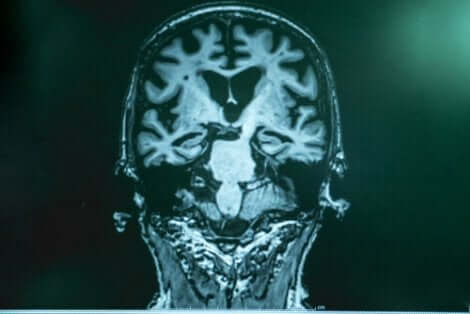

Dr. Lopera förklarar att vid Alzheimers bildas det en sorts ansamling av “skräp” i hjärnan. Denna består av ett protein som kallas amyloid. Fragment av detta klibbar ihop sig och bildar ett slags “klister” som fäster sig vid nervcellerna och ger upphov till olika funktionsstörningar i hjärnan. Den andra delen av detta “skräp” är tau, som omsluter nervcellen, “låser” in den och dödar den. Tau är mer skadligt.

Efter noggranna undersökningar i Boston fann experterna att patientens hjärna var fylld med amyloid, och till och med mer så än i andra fall. Däremot hade hon ytterst lite tau. Forskningen gjorde det möjligt för dem att bekräfta att det hos just denna patient förelåg en annan mutation som hämmade produktionen av tau och det var detta som försenade sjukdomsförloppet.